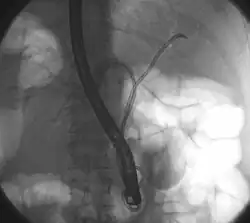

Klatskin tumor during ERCP. Wires were inserted into the left and right biliary systems. Both parts were injected through a tube with contrast, but there is no contrast visible in the area of confluence of the two systems | |